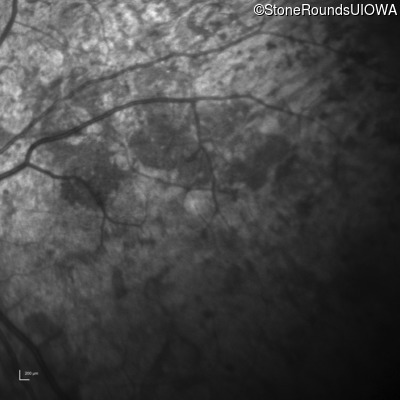

Infrared Fundus Photograph - Right - Light Perception

Exemplar

Infrared Fundus Photograph - Left - Light Perception